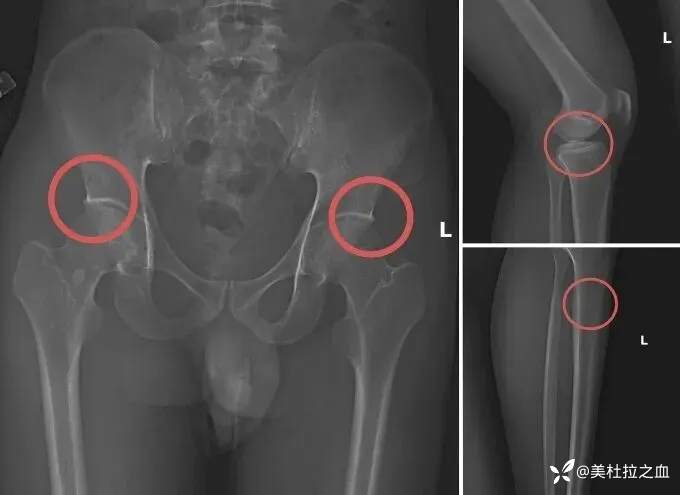

案中主谋是原锦溪县医疗中心(Trung tâm Y tế huyện Cẩm Khê)的卫生系统干部谢明洲(Tạ Minh Châu)。他竟利用自身的专业医学知识,策划并实施了一套系统性的骗保流程:先是诱使他人购买高额人寿保险,随后亲自为他们注射麻醉剂,在受害者意识不清的情况下,使用钉锤等工具,冷酷地凿断他们的骨骼,人为制造出与真实事故几乎无法区分的骨折痕迹。

他还知道哪些部位的骨折能获得最高额的赔偿,从而在作案时能够"精准下手",刻意在赔付率高的骨骼位置制造伤害。这种利用专业知识进行的犯罪,极具隐蔽性和欺骗性,使得保险公司在常规审核中难以察觉异常,误以为这些是真实的意外伤害事故。

这是该团伙进行麻醉和骨科手术的现场